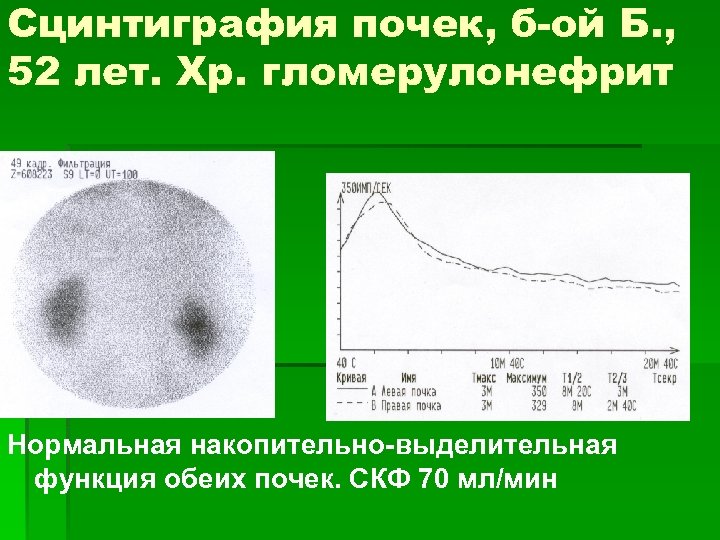

Сцинтиграфия почек, б-ой Б. , 52 лет. Хр. гломерулонефрит Нормальная накопительно-выделительная функция обеих почек. СКФ 70 мл/мин